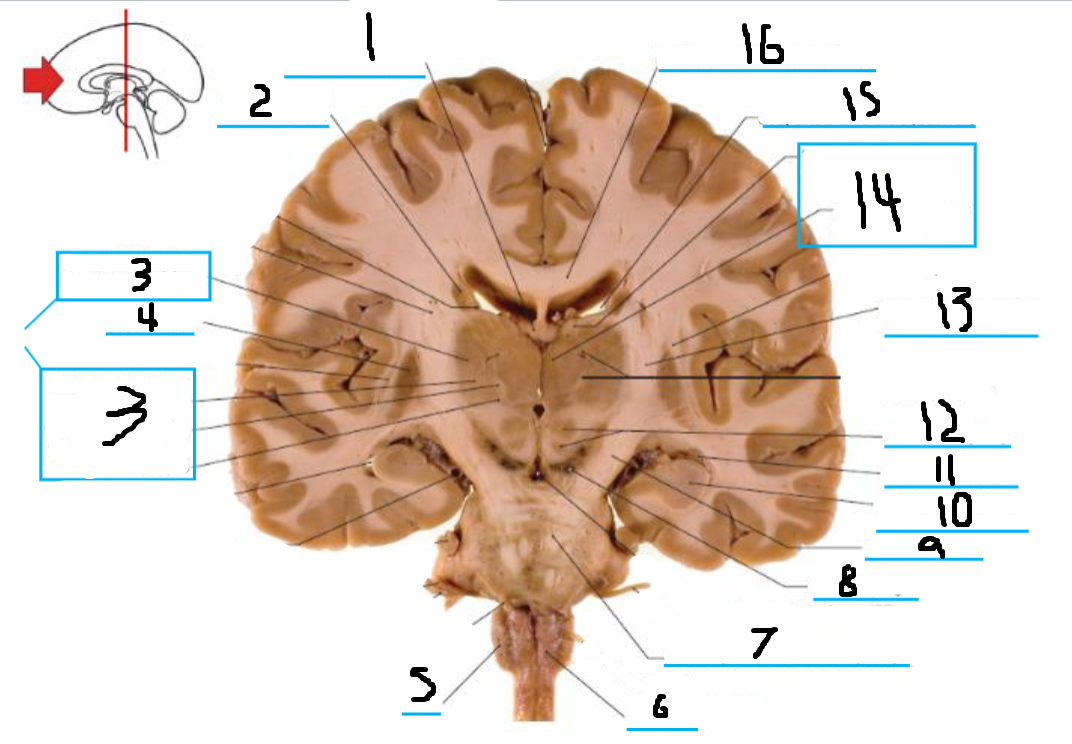

#3 and #16 are the:

Thalamus

#4 is the:

Hypothalamus

#5 and #9 is the:

Hippocampus

#6 is the:

Crus Cerebri

#7 is the:

Basilar Pons

#8 is the:

Mammillary Body

#10 is the:

Caudate

#11 is the:

Third Ventricle

#12 is the:

Globus Pallidus

#13 is the:

Insula

#14 is the

Putamen

#15 is the:

Internal Capsule

#17 is the:

#18 is the:

Lateral Ventricle

#19 is the:

Corpus Callosum